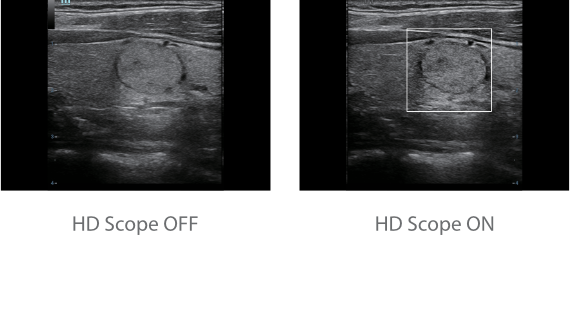

Since the company was founded, Mindray has been continuously exploring new ways to improve diagnostic confidence. Powered by the most revolutionary ZONE Sonography? Technology, Resona 7ŌĆÖs new ZST+ platform brings ultrasound image quality to a higher level by zone acquisition and channel data processing.